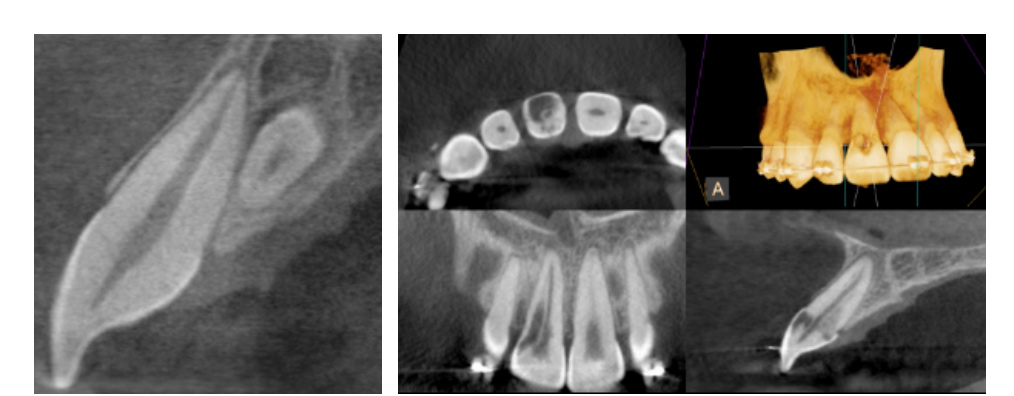

Clinical applications of CBCT technology in endodontics include the following:

Occasionally, dental defects or pathology that deem a tooth non-restorable will be revealed on a CBCT scan. If this happens, the endodontist will advise you that the tooth cannot be saved.

(Pictures of missed canal, vertical root fracture, extra tooth, and resorption)